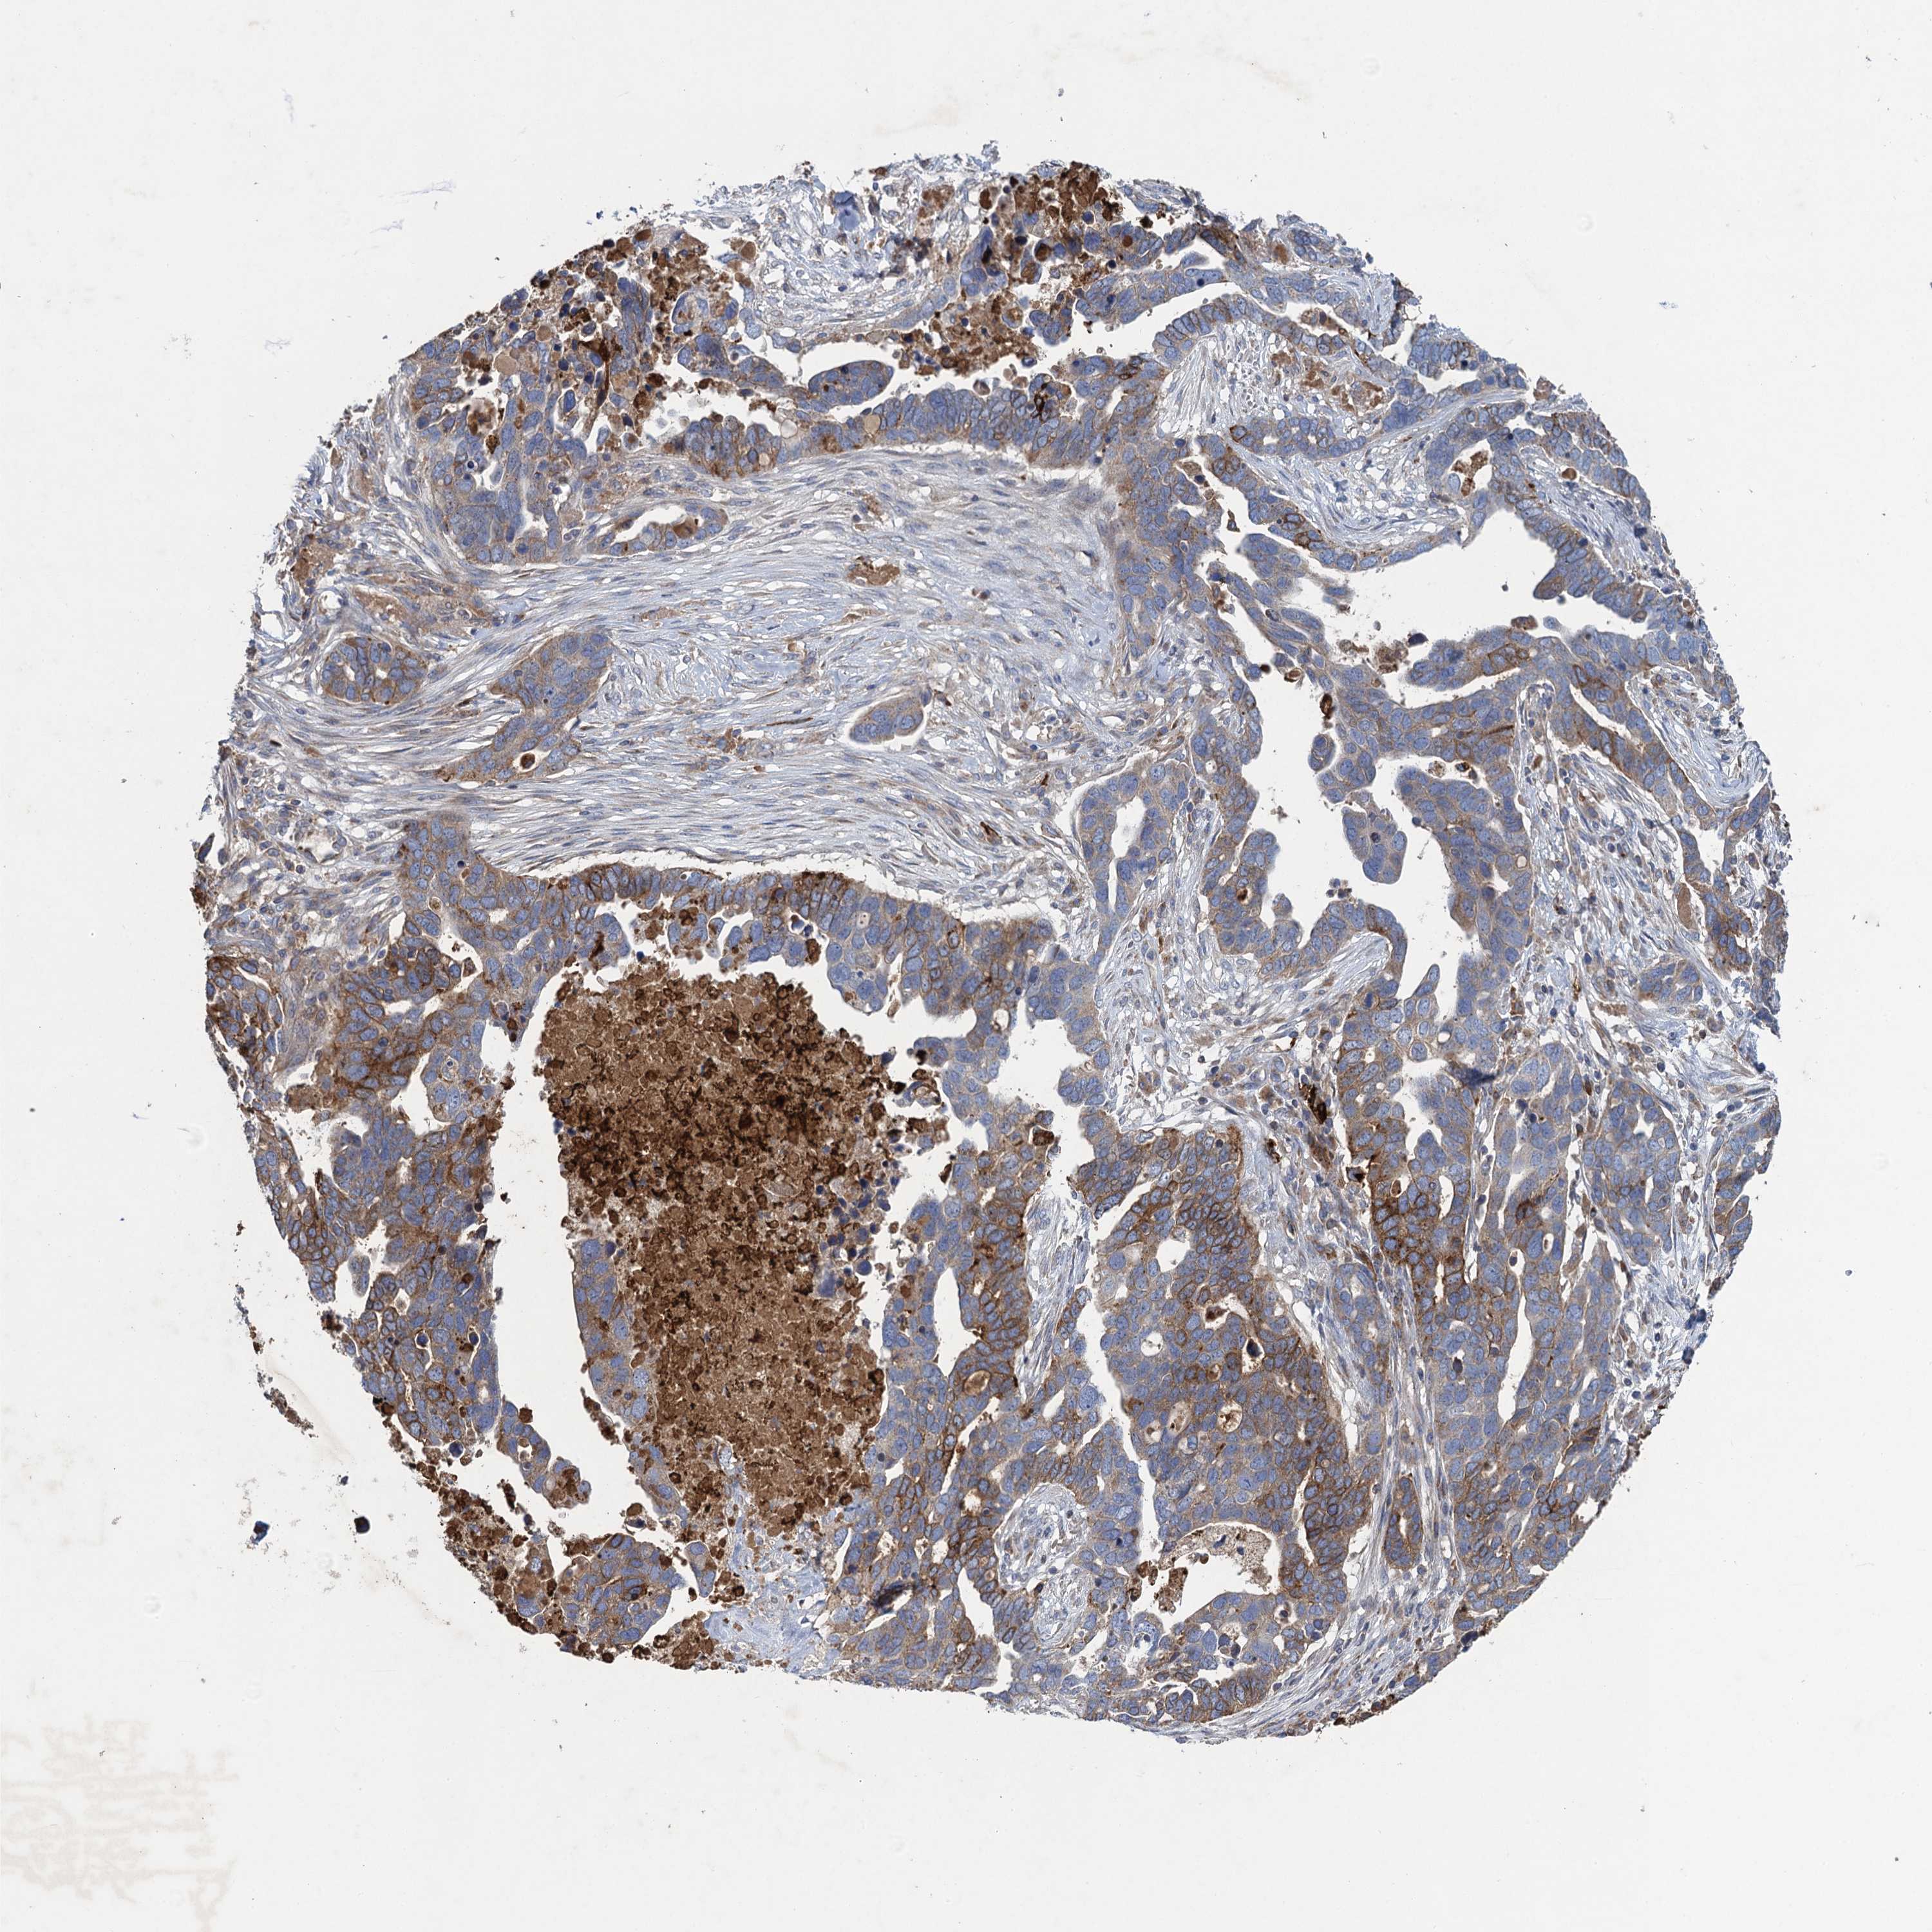

OVARIAN CANCER - Protein expressioni

A mouse-over function shows sample information and annotation data. Click on an image to view it in a full screen mode. Samples can be filtered based on level of antibody staining by selecting one or several of the following categories: high, medium, low and not detected. The assay and annotation is described here.

Note that samples used for immunohistochemistry by the Human Protein Atlas do not correspond to samples in the TCGA dataset.

Antibody stainingi

Antibody staining in the annotated cell types in the current human tissue is reported as not detected, low, medium, or high, based on conventional immunohistochemistry profiling in selected tissues. This score is based on the combination of the staining intensity and fraction of stained cells.

Each image is clickable and will lead to virtual microscopy that enables deeper exploration of all samples and also displays staining intensity scores, fraction scores and subcellular localization as well as patient and tissue information for each sample.

Antibody HPA041174

Antibody HPA041390

Cystadenocarcinoma, mucinous, NOS